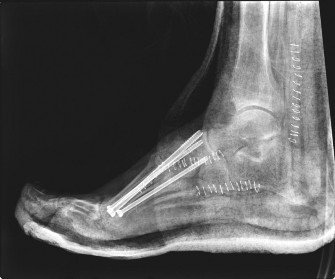

Chronic/Consolidation (Eichenholtz Stage III - Reconstruction):

Characterized by consolidation and remodeling of fragmented bone, although often with residual deformity (e.g., rocker bottom). Sclerosis and hypertrophy may be present. This is the stage often requiring surgical intervention for stability and plantigrade foot.

[Example of an acute Charcot midfoot showing early fragmentation and disorganization.]